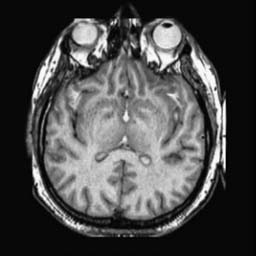

To demonstrate the effectiveness and efficiency of the proposed image fusion method , we conduct a set of comparative experiments on three image datasets. The first is composed by 8 pairs of multi-modal medical images and the second one contains 15 pairs of multi-focus gray or color natural images. These two datasets are often used in many related papers and some examples are shown in Figure 3(a) and Figure 3(b). The third one is a new multi-focus cervical cell image dataset collected by ourselves, which consists of 15 groups of color images and each group contains a series of multi-focus cervix cell images with size of or , etc. Some source examples are shown in Figure 3(c). Our source code implemented in C++ along with the new multi-focus cervical cell image dataset is available online.

We first evaluate the performance of the proposed method under varying total number of octaves and number of layers sampled per octave. The fused images of a pair of multi-modal medical images with different and are shown in Figure 4. In this example, on the one hand, when only 1 or 2 octaves are involved in constructing the DoG pyramid, the fused images fail to keep the integrity information of large size objects (e.g. eyeballs), while by increasing the value of , the integrity information of eyeballs is preserved. On the other hand, although not as significant as the increase of octave numbers , the fused image can contain more details by the increase of layer numbers . The corresponding objective quality metrics are shown in Figure 5. As shown in Figure 5(a), most of the metric values are improved as the number of octaves increases with the fixed layer numbers 3 in the global tendency and each of them tends to be stable when the number of octaves is 5. To get a relatively good quality from Figure 5(b), we can notice that some of the metric values can get a good performance when the number of layers is 3, such as the MI, SSIM, QI and VIF, though there are only a little change of all the metric values by increasing the number of layers with the fixed octave numbers 5. Because it will result in more computation burden with the increase of the value and , and for different kinds of source images, there are different performance with the diverse parameter settings. To get a trade-off between them in our experiments, we set for the multi-modal dataset, for the natural datasets and for the multi-focus cell dataset, respectively.

Figure 6 shows the fused images obtained by different methods with the multi-modal source images shown in Figure 3(a). As shown in these figures, the proposed method can produce images which preserve the complementary information of different source images well. Moreover, due to the scale-invariant structure saliency selection, our method can keep the integrity information of large size objects and the visual details simultaneously. Although the fused image generated by other methods can also capture the details to some extent, all of them fail to keep the integrity information of large size objects such as the eyeballs. Furthermore, from Figure 6(k)-6(t), the DTCWT, GFF, IM and NSCT methods may decrease the brightness and contrast while the proposed method can preserve these features and details without producing visible artifacts and brightness distortions.